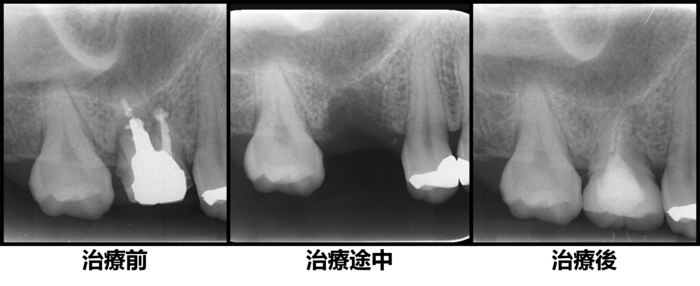

初診時デンタルX線写真

初診時デンタルX線写真とCT画像。

根管外に不透過像とそれを取り囲む透過像を認める。

コアを除去すると、分岐部へつながるパーフォレーションを認めた。

これが排膿の原因であったため、保存は困難と判断した。